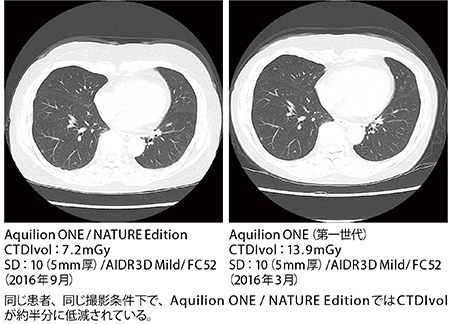

Aquilion ONE/NATURE Editionの“pureViSION Optics”は、X線の出力から検出器までを最適化することで被ばく線量の低減と画質向上を両立させている。同院でAquilion ONE(第一世代)とAquilion ONE/NATURE Editionで撮影された同一患者の胸部CT(同じSD)を比較したところ、CTDIvolが13.9から7.2になり、領域別では頭部で40%、胸部46%(心臓30%)、腹部48%の線量低減となった。永田主任は、「同じADCTであり、画像再構成法(AIDR 3D)も変わらないことから、線量には大きな差はないと考えていましたが、大きく削減されていることがわかりました。これは、新しいX線光学技術であるpureViSION Opticsの効果と思われます」と述べる。

■Aquilion ONE(第一世代)とAquilion ONE/NATURE EditionのCTDI差